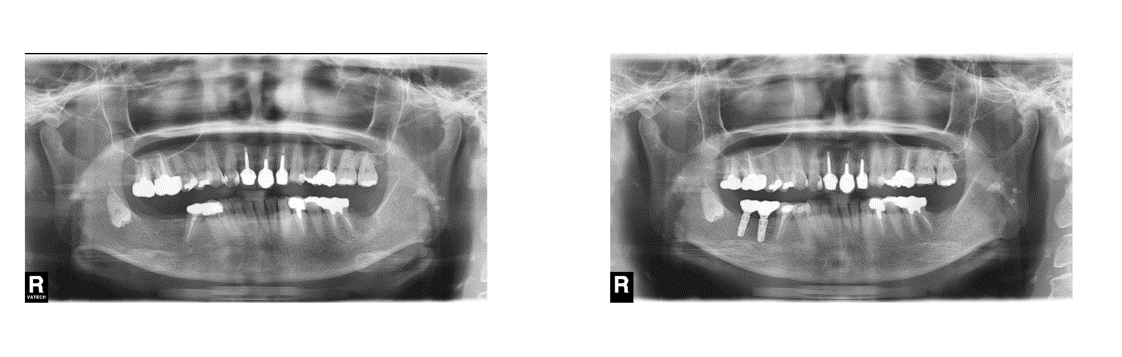

インプラント治療の症例6

(上下の歯が複数本ない・咬合崩壊)

治療前

治療後

| 診断名・主訴 | ①治療の続きをしてほしい ②インプラント希望 |

| 年齢 | 50歳 |

| 治療期間 | 3年間 |

| 治療内容 | インプラント治療 |

| 治療に用いた主な材料、設備機器 | 京セラFINESIAインプラント 上部構造:ジルコニアセラミック |

| 抜歯部位 | 右上8・6・2 左上5・6 |

| 治療費 | 約350万 |

| リスク・副作用 | 術後出血や腫れ |